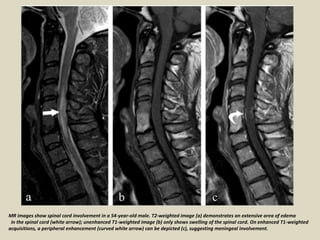

MR images show spinal cord involvement in a 54-year-old male. T2-weighted image (a) demonstrates an extensive area of edema

in the spinal cord (white arrow); unenhanced T1-weighted image (b) only shows swelling of the spinal cord. On enhanced T1-weighted

acquisitions, a peripheral enhancement (curved white arrow) can be depicted (c), suggesting meningeal involvement.